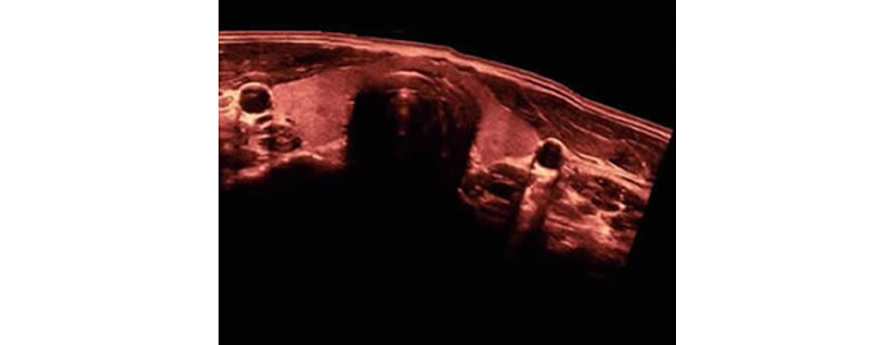

iScape?

Pozwala na uzyskanie pe?nego i poszerzonego podgl?du struktury anatomicznej poprzez zastosowanie obrazowania panoramicznego, w po??czeniu ze wskazaniem pr?dko?ci i mo?liwo?ci? skanowania w prz├│d/w ty?. Dzi?ki temu skanowanie jest znacznie ?atwiejsze, p?ynniejsze i bardziej kontrolowane.